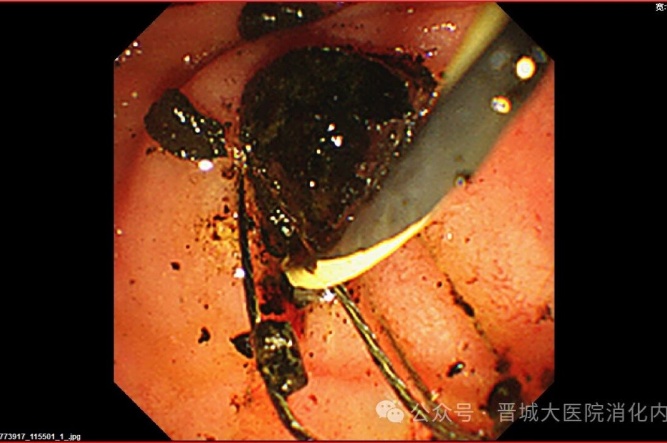

手術(shù)中,普通外科首先為李阿姨行“腹腔鏡膽囊切除”(LC),消化內(nèi)科團隊緊隨其后行ERCP,造影發(fā)現(xiàn)膽總管內(nèi)有多個巨大結(jié)石,最大約2.5×2.1厘米,且結(jié)石堅硬,形如煤渣樣,使用取碎石一體網(wǎng)籃多次反復(fù)碎石、取石。用生理鹽水反復(fù)沖洗膽道,無結(jié)石殘留。利用微創(chuàng)技術(shù)順利完成膽囊切除及膽總管結(jié)石取石,手術(shù)時間短、創(chuàng)傷小、恢復(fù)快。